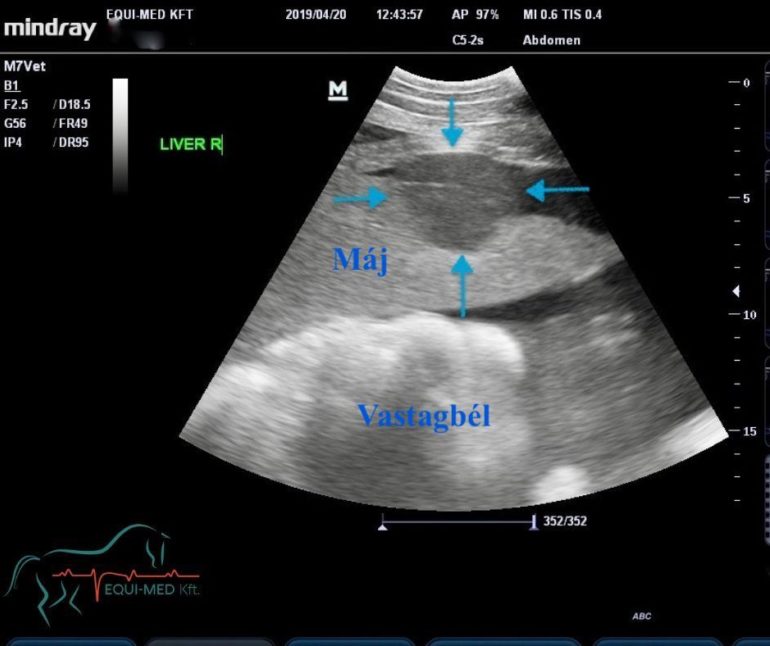

Az ultrahang az egyik legfontosabb diagnosztikai eszköz, ami az elmúlt évtizedekben került be a kiegészítő vizsgálatok sorába és igazi áttörést hozott a belgyógyászati betegségek diagnosztizálásában és kezelésében. A vizsgálathoz a legtöbb esetben nem szükséges a szőrt lenyírni (kivéve, ha nagyon hosszú), és a legtöbb lovat bódítani sem kell. Egy megfelelő ultrahanggal egyedülállóan jól vizsgálható az összes belső szerv (pl.: lép, a máj, a vesék, emellett a vékony-, és vastagbelek, a gyomor, a rekesz, a hashártya; valamint csikókban a köldökstruktúrák) és akár már néhány milliméteres elváltozások is észrevehetők.